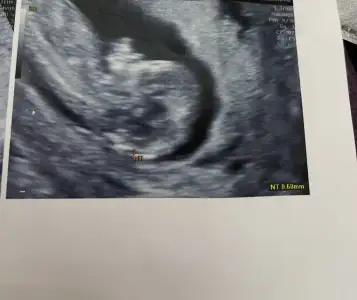

Ayy bende senin gibiyim aynı canım 13+3teyiz şuan aklım hep bebekte. Bir hareketlerini hissedebilseydikHaha mantıklı evet. Ama üç gündür iyi hissetmediğim için bebeği de merak ediyorumiçgüdüsel işte

Ayy bende senin gibiyim aynı canım 13+3teyiz şuan aklım hep bebekte. Bir hareketlerini hissedebilseydikHaha mantıklı evet. Ama üç gündür iyi hissetmediğim için bebeği de merak ediyorumiçgüdüsel işte